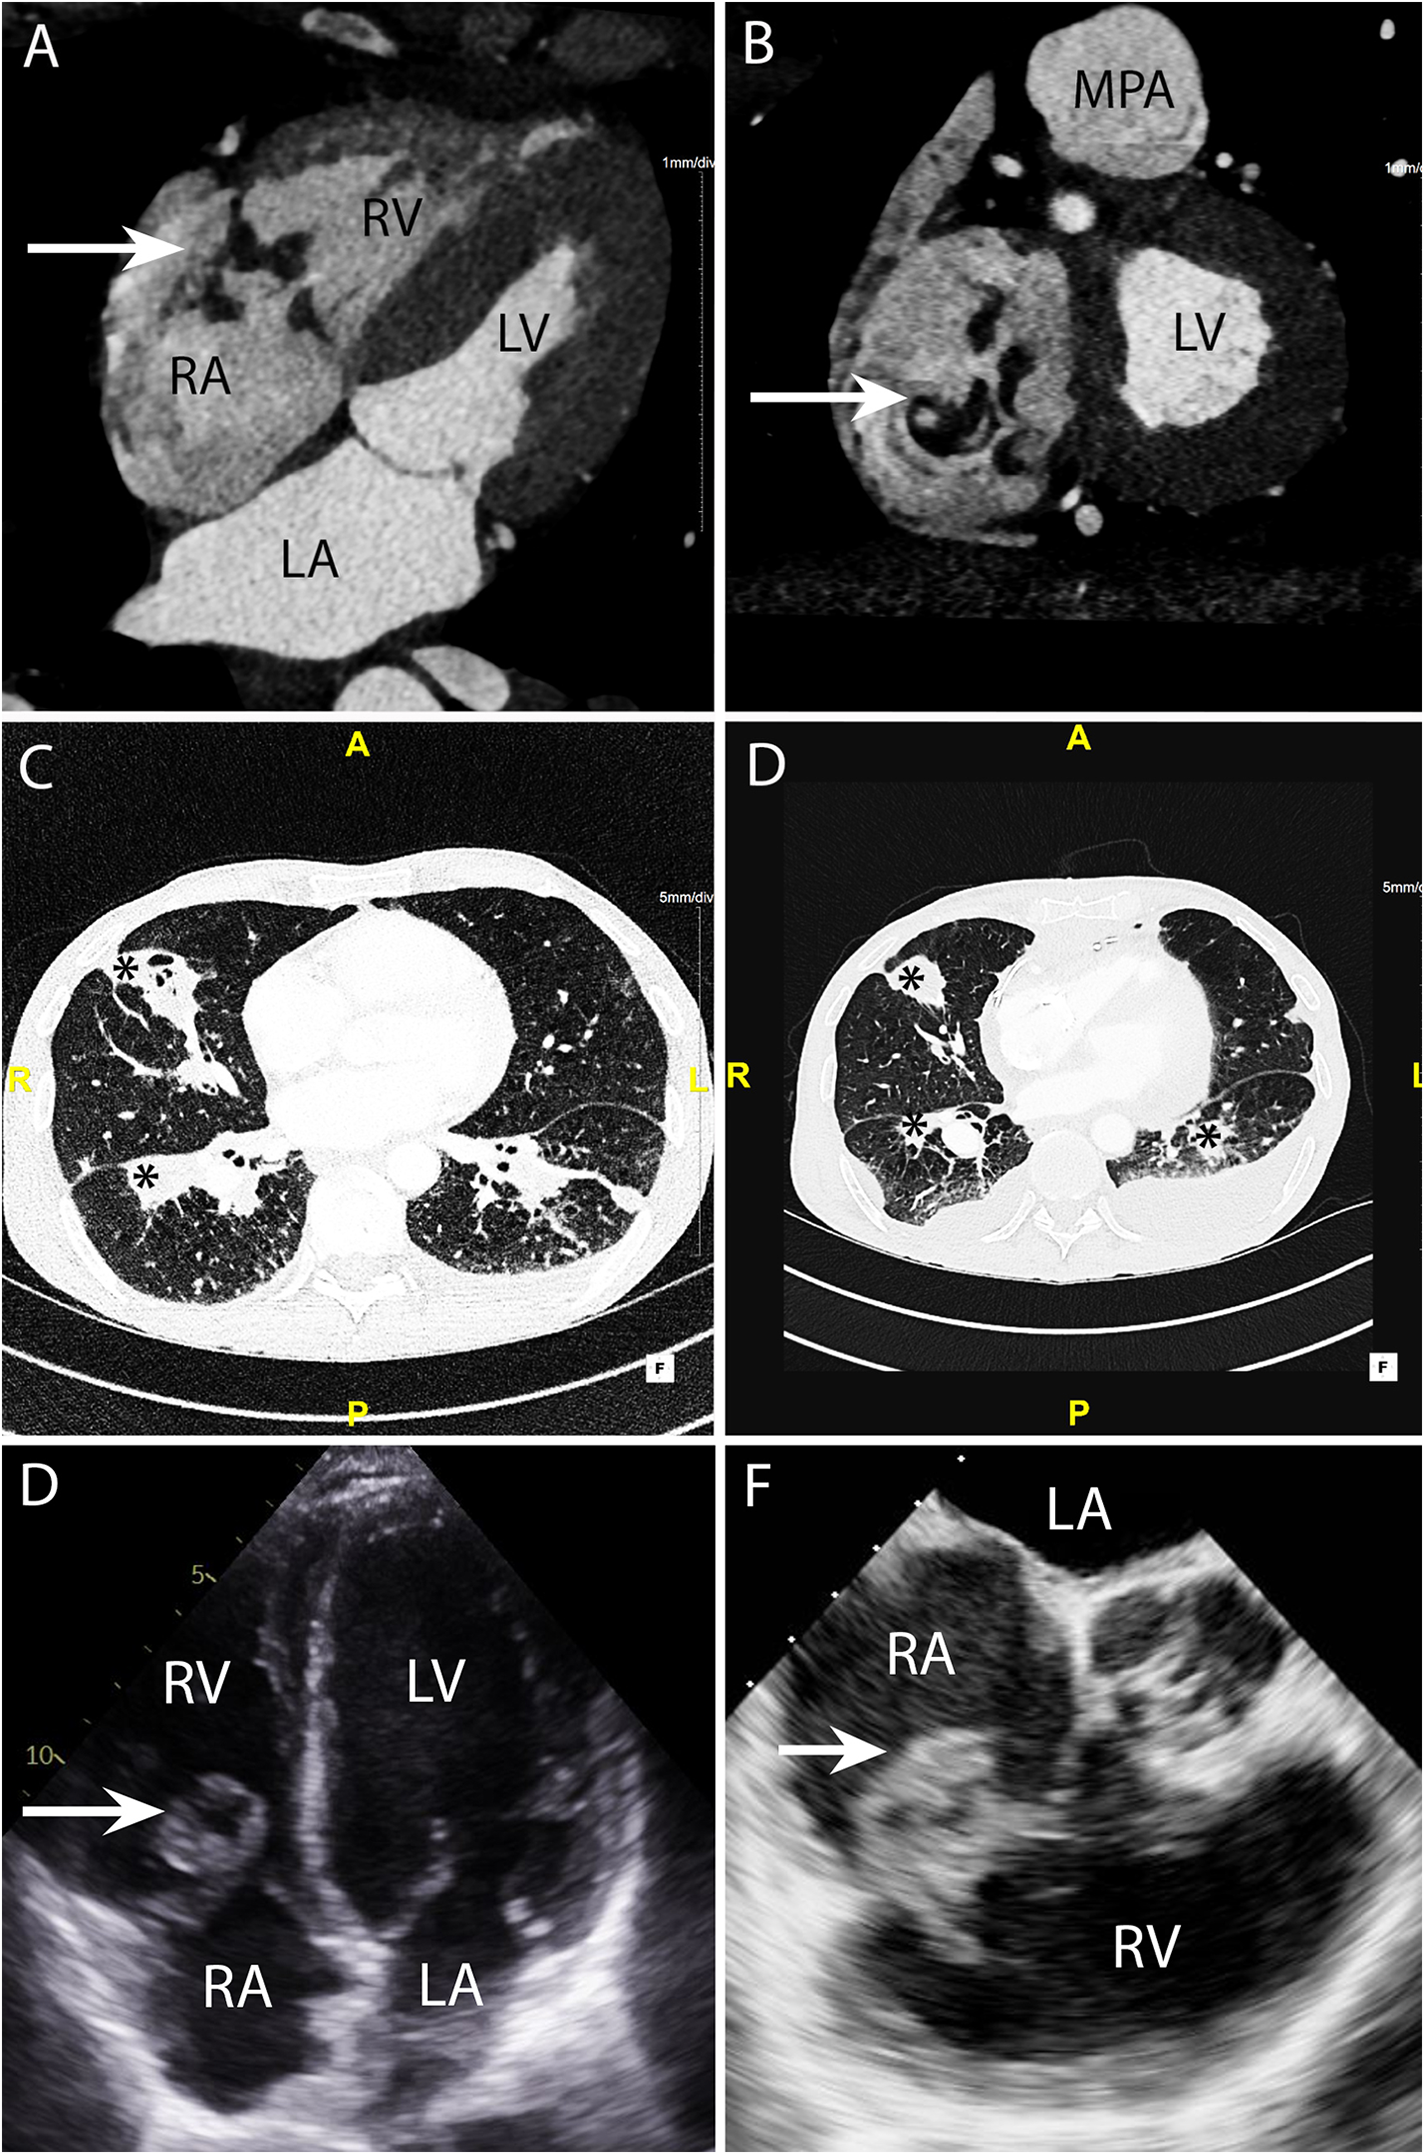

Figure 5

CASE 5 - A 53-year-old man presented with fever, dyspnoea and confusion on a backgound history of intravenous drug use. Blood cultures grew Staphylococcus aureus (see text). RA, right atrium; RV, right ventricle; MPA, mean pulmonary artery; LA, left atrium; LV, left ventricle.

A 53-year-old man presented with fever, dyspnoea and confusion on a backgound history of intravenous drug use. Blood cultures grew Staphylococcus aureus. CT brain imaging showed a subarachnoid haemorrhage. Cardiac CT was performed: Axial 4-chamber (Figure 5A) and oblique coronal (Figure 5B) views showed a low density soft tissue vegetation (arrow) (HU 59) attached to the tricuspid valve leaflets with an associated perforation (arrow) over the posterior tricuspid valve leaflet (Figure 5B). The wide field of view reconstructions (Figures 5C and 5D) showed bilateral foci of cavitating consolidation consistent with septic emboli (asterisks). Prior to CT, a TTE and TOE were performed. TTE 4-chamber (Figure 5E) and TOE ME AV SAX (Figure 5F) views demonstrated a large mobile heterogenous mass consistent with a large vegetation. A cardiac CT and a flash ECG-gated aorta were arranged to further elucidate leaflet morphology, assess for extra-cardiac complications and evaluate the coronary arteries prior to surgical intervention.

Figure 6

CASE 6 - A 71-year-old man presented with fever, confusion and fatigue. Enterococcus faecalis was isolated from blood cultures (see text). RA, right atrium; RVOT, right ventricular outflow tract; RV, right ventricle; MPA, mean pulmonary artery; LA, left atrium; LV, left ventricle; AAo, ascending aorta.

Case 6

A 71-year-old man presented with fever, confusion and fatigue. Enterococcus faecalis was isolated from blood cultures. Cardiac CT was performed: An oblique coronal (Figure 6A) view demonstrated a paravalvular fistula (arrow) extending from the region of the aortic valve non-coronary cusp (NCC) and left ventricular outflow tract into the right atrium (RA). An oblique axial view (Figure 6B) demonstrated a pseudoaneurysm (asterisk) (HU 283) originating from the right coronary cusp (RCC). An oblique in-plane view (Figure 6C) demonstrated both the pseudoaneurysm (asterisk) originating from the RCC and the fistulous connection (arrow) between the NCC and RA. Preceding TTE images in the apical 5-chamber view (Figure 6D) demonstrated a likely communication between the aortic valve and LVOT. Blood flow through this communication was documented with both apical 5-chamber colour Doppler (Figure 6E) and subcostal 4-chamber pulsed wave Doppler (Figure 6F). A subsequent CT was performed to delineate the fistulous connections more definitely. The CT scan also confirmed a small anterior aortic root pseudoaneurysm that had not been suspected on the TTE.